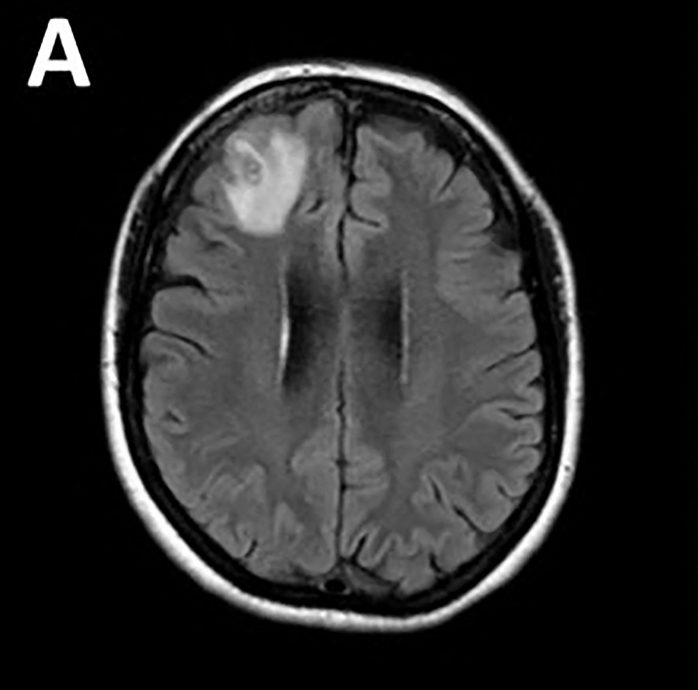

医生们对于一名64岁澳洲妇女开始出现记忆差错问题的起因感到困惑,对她进行核磁共振造影(MRI)检查后发现她的脑前方有“非典型病变”。那是一条长达8公分的“蛇蛔属”(Ophidascaris robertsi)蛔虫。研究人员指称,这是在袋鼠和毡蟒体内常见的寄生虫,但人类体内并不曾见。

这条寄生虫在脑部扫描之下呈现“弦状结构”,之后通过脱氧核糖核酸(DNA)检测确认。